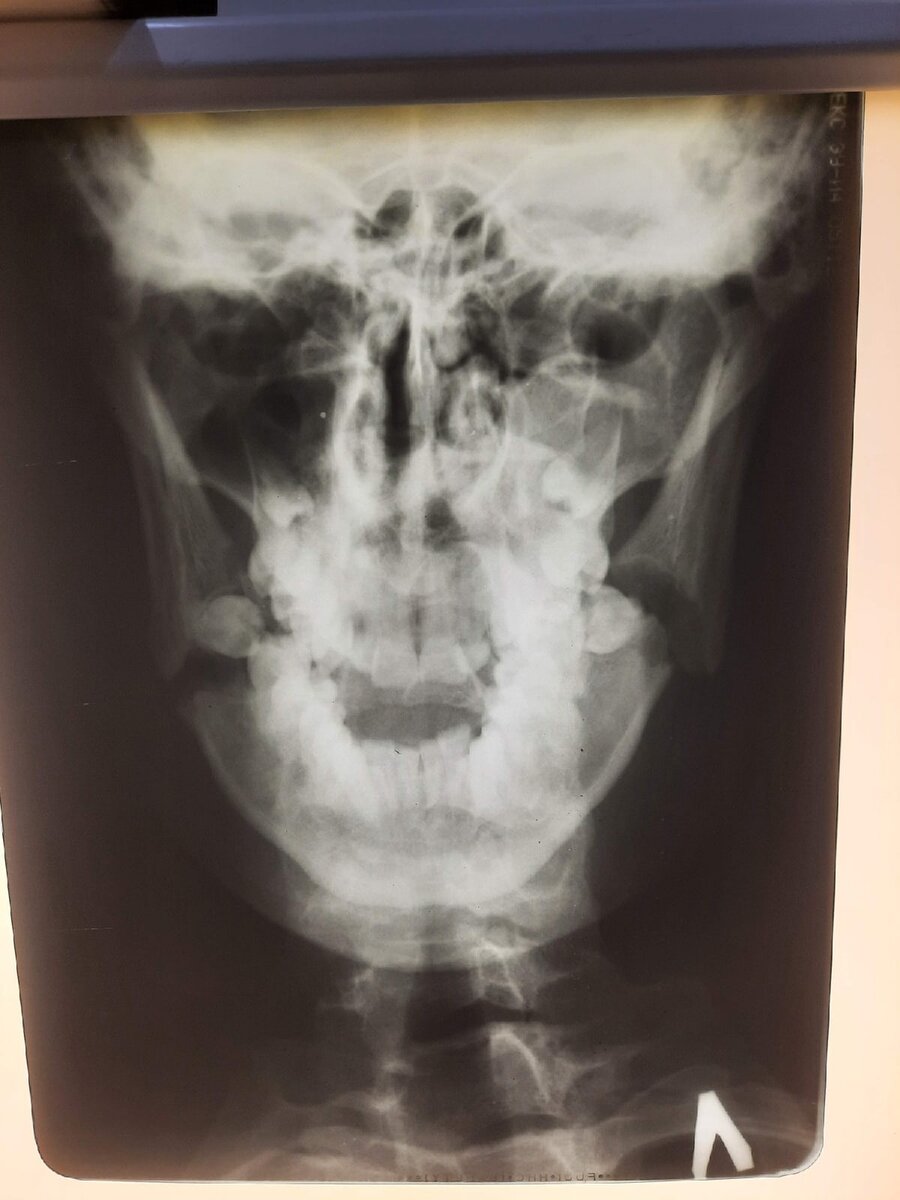

Спойлер - плохо! Этот случай в очередной раз подтвердил мои выводы о том что у некоторых людей инстинкт самосохранения атрофирован. Было обычное субботнее дежурство. Пациенты шли в среднем темпе. И вот, около двух часов ночи привозят пациента. Мужчина примерно 30-35 лет, в алкогольном опьянении( куда-же без этого). Выпивал с друзьями и в один момент случился конфликт и пациент получил удар в нижнюю челюсть. После чего появились жалобы на ограничение движений и боль в нижней челюсти. Фельдшер скорой помощи который привез этого мужчину уверял меня что у мужчины простой вывих и в принципе рентген снимок можно не делать, вправить вывих и отпустить пациента домой. Но после пальпации я почувствовал нарушение целостности кости в областях углов нижней челюсти и всё же решил сделать рентген снимок. Снимок показал не очень веселую картину для мужчины, а именно двусторонний перелом нижней челюсти в области углов со смещением. Пациент ввиду измененного сознания не до конца понял всю тяжесть своей ситуации и по началу ехать в стационар не хотел, мотивируя это тем что он поспит и все пройдет. Я ,наверное, 20 минут объяснял мужчине методы лечения данной травмы, и возможные последствия если эту травму не лечить. Пациент всё же согласился. Я написал направление и со спокойной душой отправил его на дальнейшее лечение в стационар. Но самое интересное было на следующий день! Я позвонил врачу травматологу который дежурил в тот день. И на мое удивление пациент написал отказ от стационарного лечения и отправился домой. Я был мягко говоря удивлен его поступком учитывая то, что и я, и врач в стационаре ему достаточно подробно все объяснили. Однако, через 2 дня этот пациент опять обратился в травмпункт с острой болью в области углов нижней челюсти. Я про таких говорю кушать захочет, придет! Естественно пациент был уже трезвый, отек в области нижней челюсти заметно увеличился с последнего раза когда я его видел. Но даже этих двух дней хватило для того что-бы увеличить срок лечения, шанс возникновения возможных осложнений и срок дальнейшей реабилитации. Пациент был повторно направлен в стационар и на этот раз он согласился на госпитализацию и дальнейшее лечение.